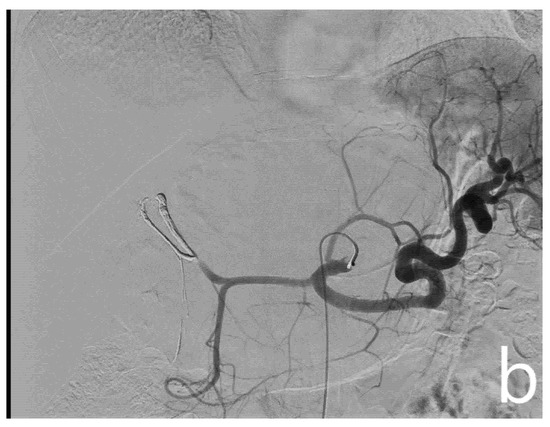

After confirmation of the feeding arteries, superselective catheterization of the single feeding vessel was obtained using a microcatheter (Boston Scientifics, Marlborough, MA, USA); embolization was achieved using polyvinyl alcohol particles (PVA), whose size varied, depending on the caliber of the feeding artery. In patients planned for major hepatectomies, whenever a wide feeding artery was identified, ethylene-vinyl alcohol copolymer (EVOH)-based liquid embolic agent (Squid Peri, Emboflu, Switzerland) was used to complete the embolization (Figure 2).

Figure 2.

Pre- and post-embolization angiography. A giant hemangioma with vascular afference from the left hepatic artery originating independently from the celiac trunk is identified (a). Embolization is performed with microparticles and Squid 18 to achieve complete lesion devascularization (b).